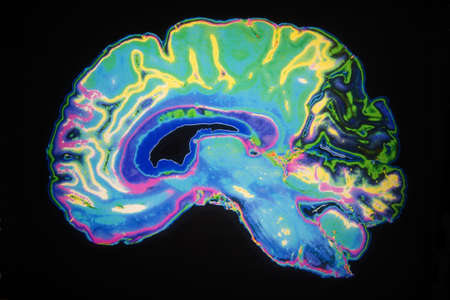

Artificially Coloured MRI Scan Of Human Brain